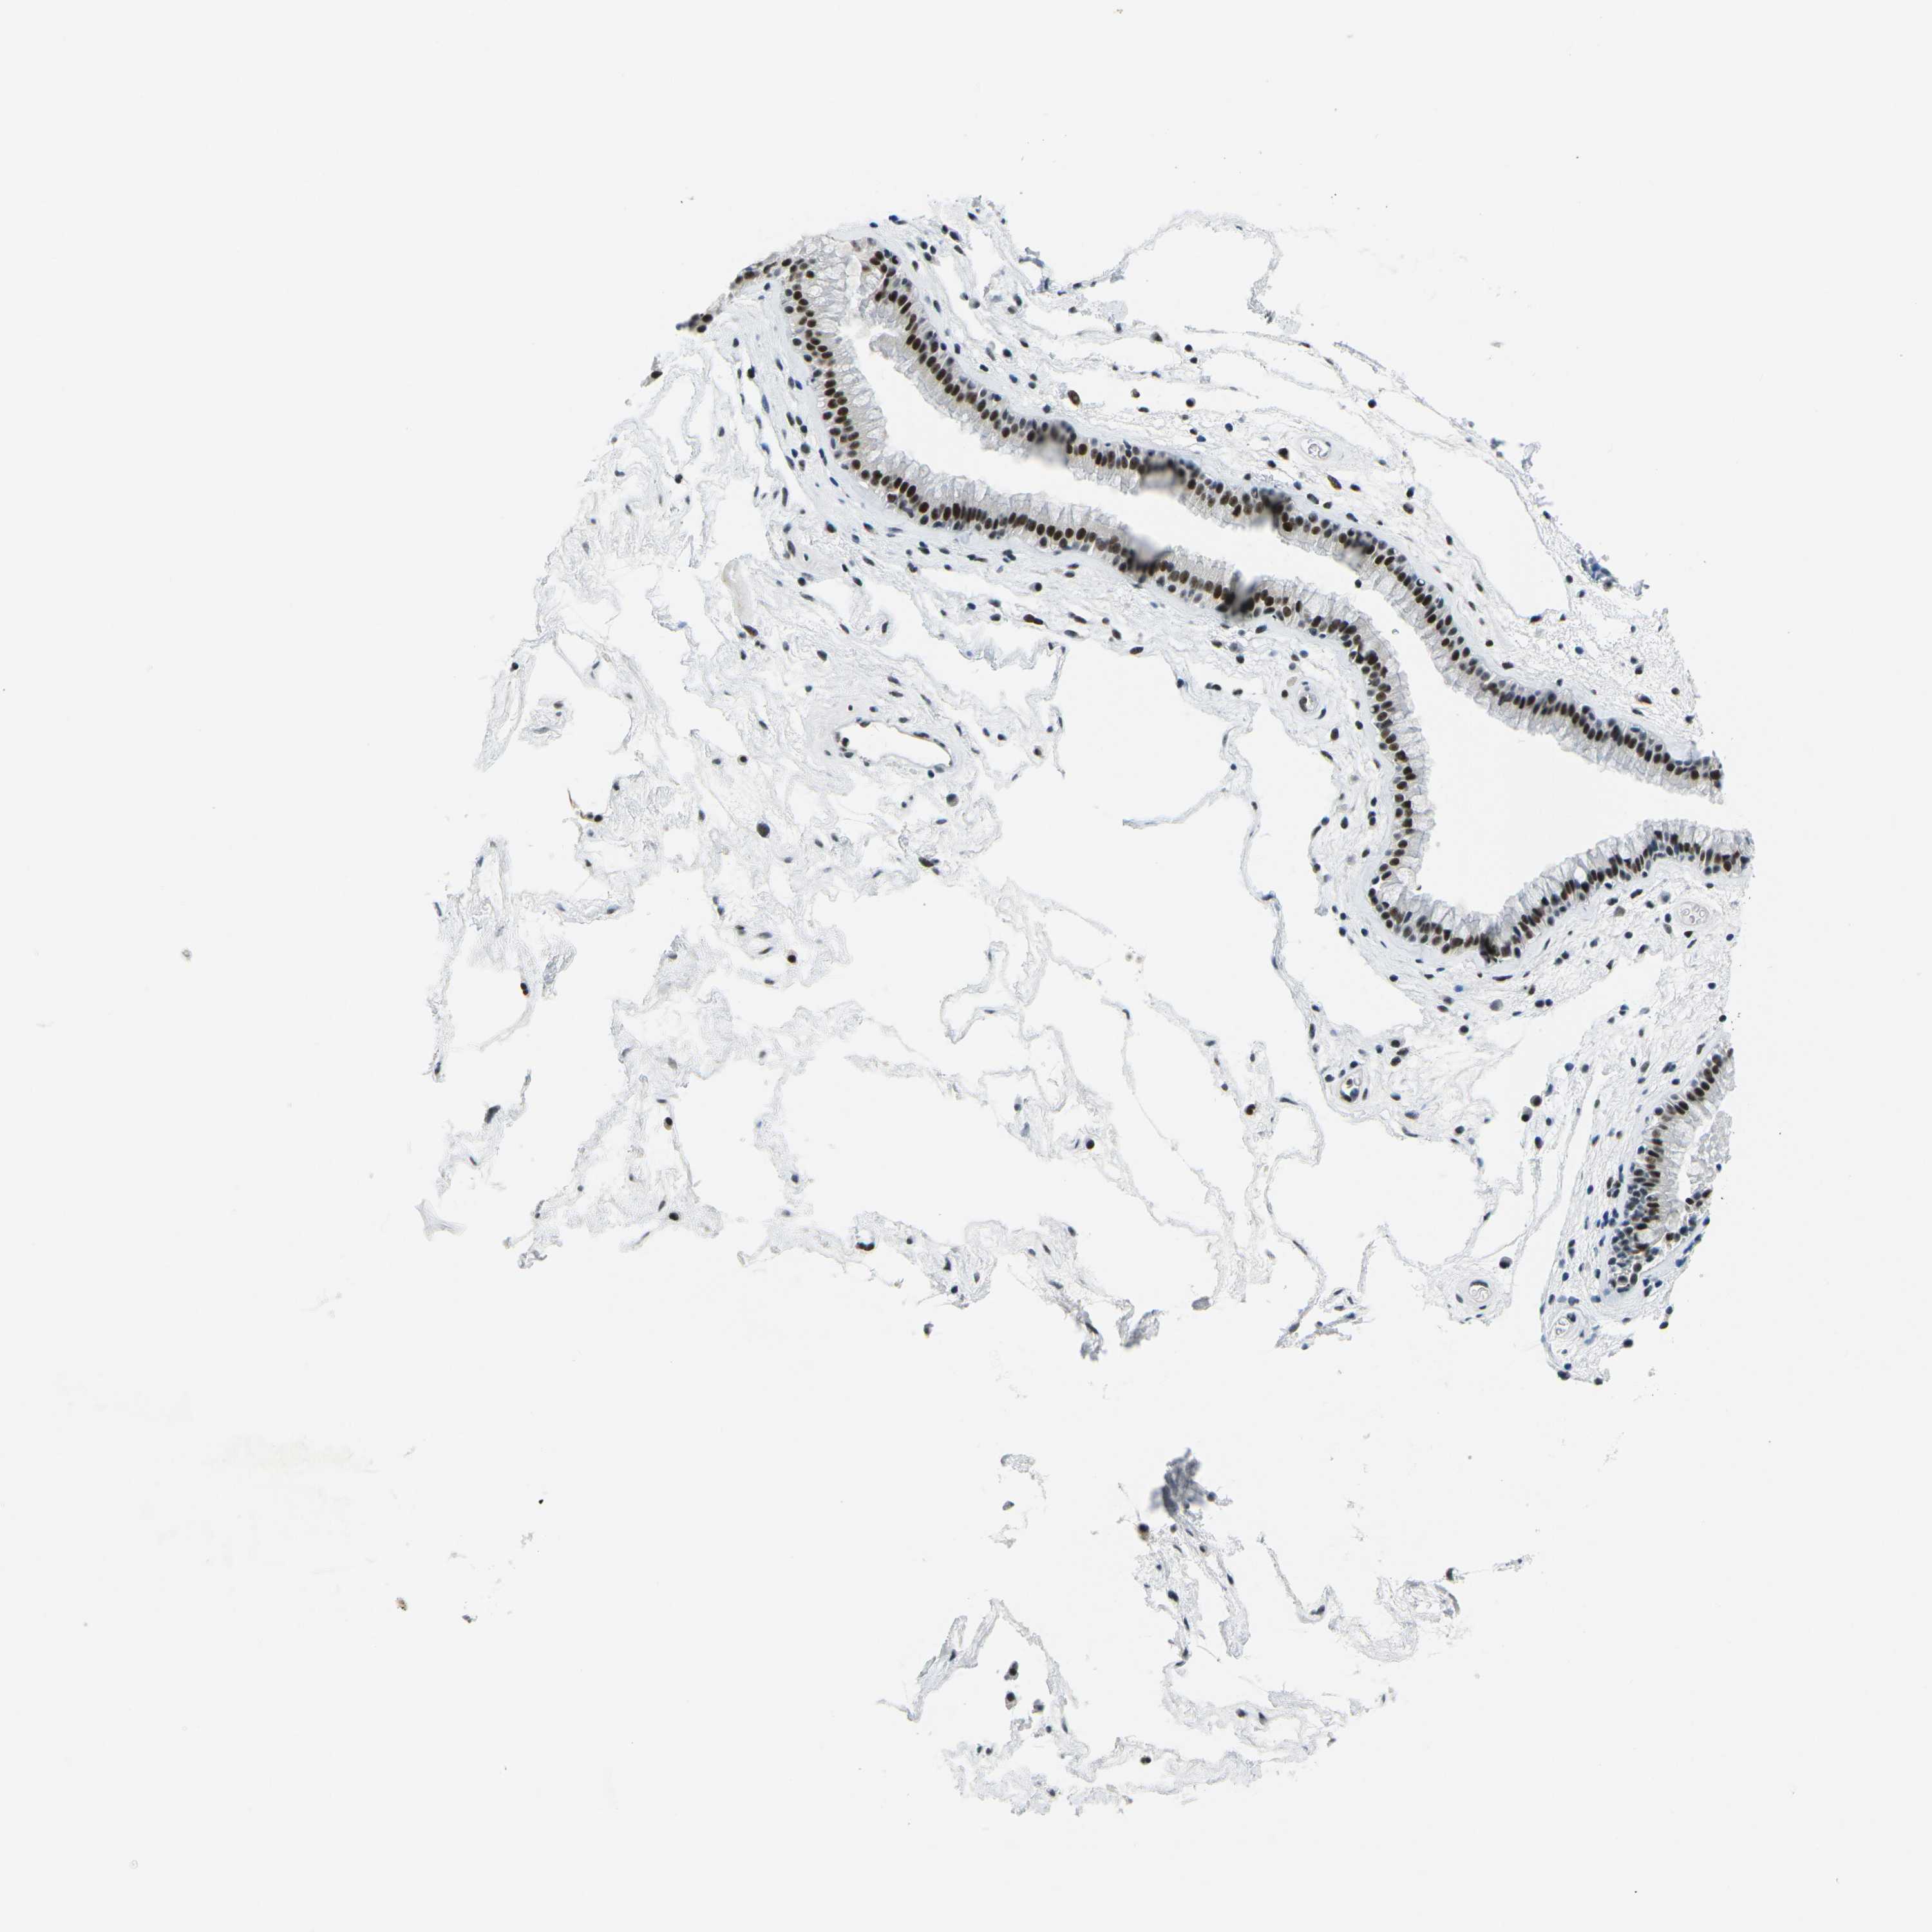

PRPF8